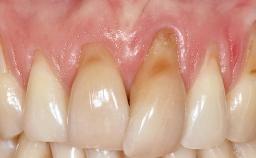

A 30-year-old woman was referred by her general dentist for evaluation of an esthetic complication related to previous implant treatment for congenitally missing maxillary lateral incisors. The patient’s chief complaint was the inadequate esthetic appearance of her smile. The case demonstrates the use of a combined approach to achieve optimal results. Two different flap designs - a tunnel technique and a coronally advanced flap - are employed based on the surgical objectives for the affected site.

Soft Tissue Anatomy Intact Defective

Soft Tissue Contour and Volume Slightly compromised